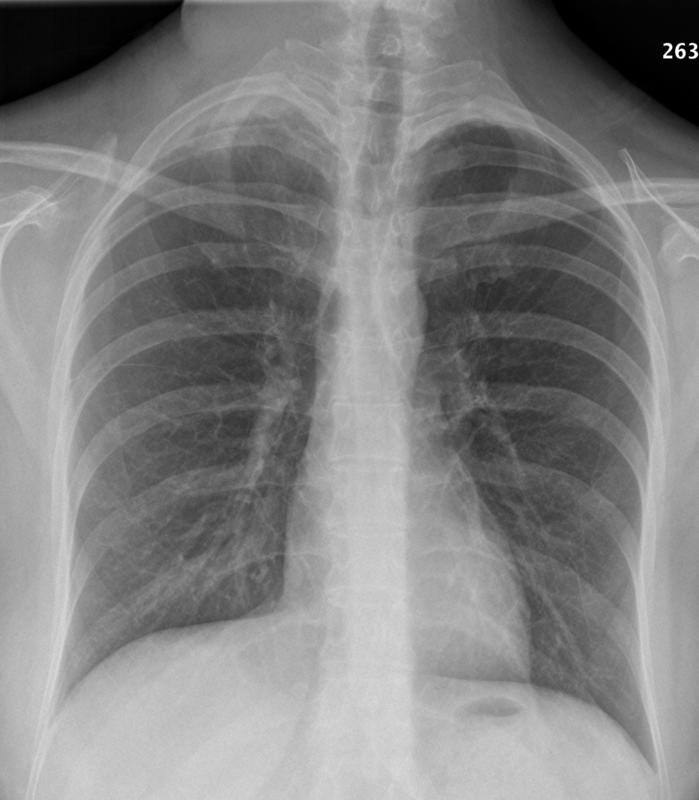

lymphoma

Rt supraclavicular nodes (NHL)